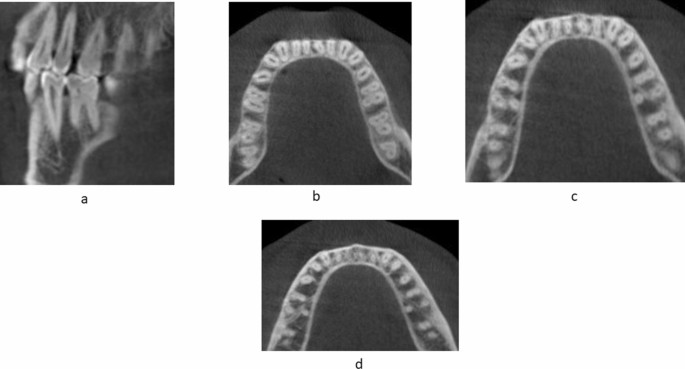

Root canal morphology of permanent MIs

A total of 400 scans were assessed to evaluate the root canal morphology of the permanent mandibular central (n = 800) and lateral (n = 800) incisors on the right and left sides. The root canal configuration of the mandibular central and lateral incisors was determined according to Vertucci’s classification. Several cross-sectional images from the cementoenamel junction to the root apex of the mandibular central and lateral incisors were studied to evaluate the anatomy of the root canals, and the canal configuration was categorized as follows:

The different levels to detect canal morphology was based on the study by Kurumboor K. In this study, the average root length of mandibular central incisor was 12.9 mm and lateral incisor was 12.83 mm. Based on this findings, each section was studied at three levels i.e. 3 mm from apex to study apical third, 6 mm from apex for middle third and 9 mm from apex for coronal third, all three studied in axial section of CBCT scans37.

The root canal morphology of the mandibular central and lateral incisors was assessed in sagittal sections at three different levels: 3 mm from the radiographic apex to assess the morphology in the apical third; 6 mm from the apex to assess the morphology of the canals in the middle third of the root; and 9 mm from the apex to assess the morphology of the canals in the coronal third of the root.

The canal configuration and the numbers of the roots and canals of the central and lateral incisors were classified according to Vertucci’s classification16.

Overall, 66.75% (534 of 800) of the mandibular central incisors showed a simple (Vertucci Type I) root canal morphology. Of the 800 central incisors evaluated, 68% (272 of 400) on the right and 65.5% (262 of 400) on the left side showed a simple canal morphology (Table 5) (p > 0.01) (Fig. 6).

Approximately 33.25% (266 of 800) of the mandibular central incisors showed a complicated root canal morphology (Type III, V, or II). Complicated root canal morphology including Vertucci’s Type II, III, IV, and V was found in 32% (128 of 400) of MCIs on the right side and 34.5% (138 of 400) of the left side. Vertucci Type III (28.3% on the right side and 31% on the left side) canal configuration was the second most common root canal morphology for the mandibular central incisors, followed by Type V and II (p > 0.01) (Table 5).

Mandibular lateral incisors

Overall, 58.62% (469 of 800) of the mandibular lateral incisors showed a simple (Vertucci Type I) root canal morphology. Of the 800lateral incisors evaluated, 58.3% (233 of 400) on the right and 59% (236 of 400) on the left side showed a simple canal morphology (p > 0.01) (Table 5) (Fig. 6).

Approximately 41.37% (331of 800) of the mandibular lateral incisors showed a complicated root canal morphology (Type III, V, or II). Complicated root canal morphology including Vertucci’s Type II, III, IV, and V was found in 41.75% (167 of 400) of MCIs on the right side and 41% (164 of 400) of the left side. Vertucci Type III (34.8% on the right side and 35.8% on the left side) canal configuration was the second most common root canal morphology for the mandibular lateral incisors, followed by Type V and II (p > 0.01) (Table 5).